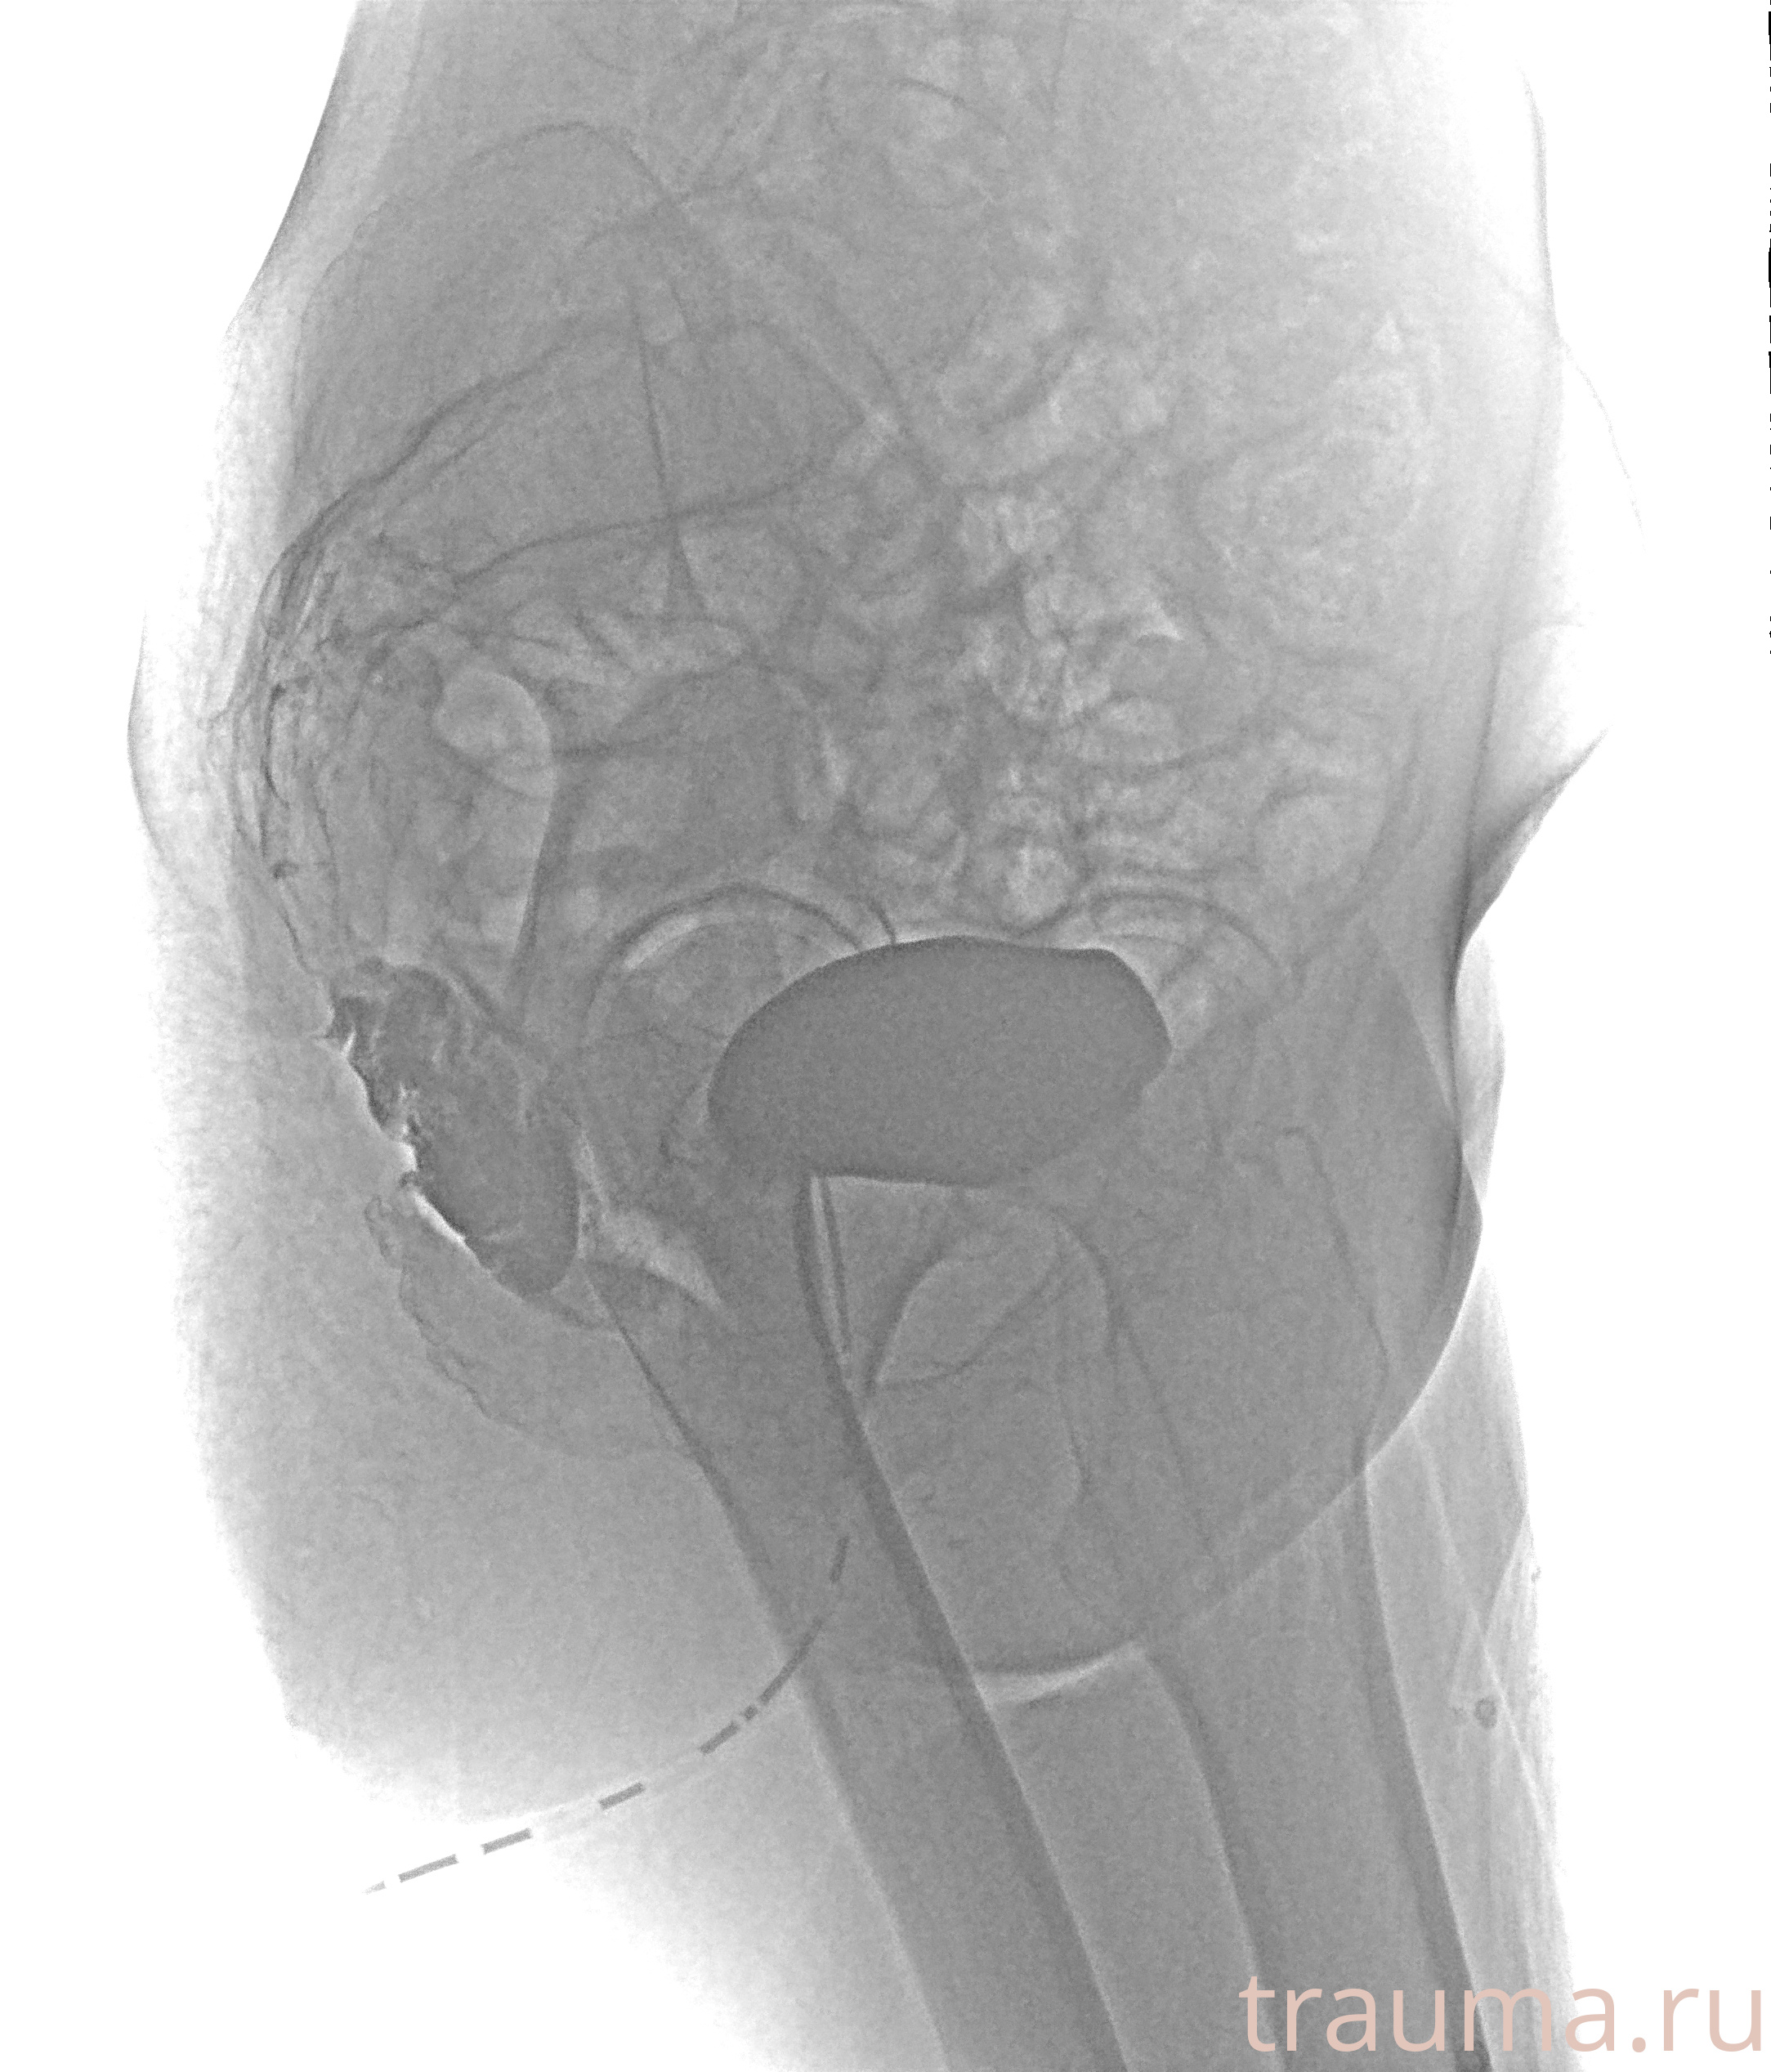

Рентгенограммы

Рентген на дому: по вашему адресу приезжает врач-рентгенолог, травматолог-ортопед с мобильным рентгеновским аппаратом, проводит диагностику травмы или заболевания, делает необходимые рентгенограммы, дает рекомендации по дальнейшему лечению. Получить качественные снимки в домашних условиях возможно благодаря уникальной методике, разработанной МосРентген Центром для института  Склифосовского